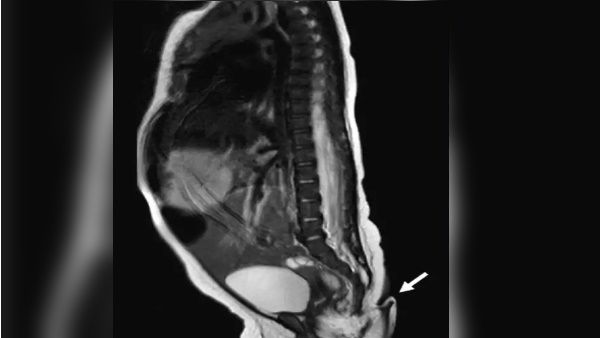

ડેઈલી સ્ટાર અનુસાર માતાને તેની ગર્ભાવસ્થા દરમિયાન કોઈ સમસ્યા નહોતી. રેડિયેશન, ચેપ વગેરેનો કોઈ અગાઉનો ઇતિહાસ પણ નહોતો. તેઓને પહેલેથી જ એક પુત્ર છે, જેનો જન્મ એકદમ સ્વસ્થ હતો. બાળકના એમઆરઆઈ સ્કેનમાં પણ મગજની કોઈ અસામાન્યતા દેખાઈ નથી. બાળક સંપૂર્ણપણે સામાન્ય અને સ્વસ્થ છે. જોકે, બાળકની સર્જરી તેના જન્મના બે મહિના બાદ કરવામાં આવી હતી.